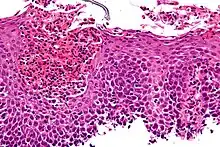

Esophagitis can be diagnosed by upper endoscopy, biopsy, upper GI series (or barium swallow), and laboratory tests.[4]

An upper endoscopy is a procedure to look at the esophagus by using an endoscope. While looking at the esophagus, the doctor is able to take a small biopsy. The biopsy can be used to confirm inflammation of the esophagus.